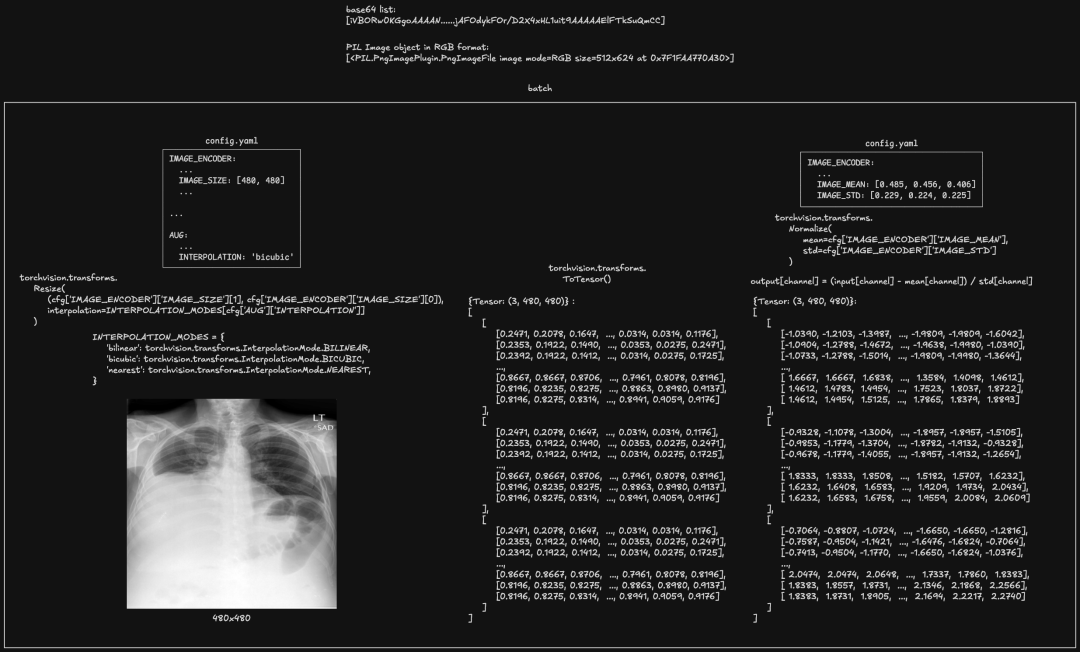

以 https://openi.nlm.nih.gov/imgs/512/145/145/CXR145_IM-0290-1001.png 作为输入图片为例,encode 编码过程可大致分为三步:

preprocess

图像以 Base64 编码的字符串形式批量传递,首先通过 base64.b64decode 解码为二进制数据,然后使用 PIL.Image.open 将其转换为 PIL Image 对象。接着,图像被 resize 到 480 x 480 的大小,并进行转张量及 normalize 操作,使其符合模型输入要求。

此阶段输出的张量形状为 [1, 3, 480, 480],其中 1 是批次大小,3 是图像的通道数(RGB),480 x 480 是图像尺寸。

预处理后的图像被输入 DaViT 模块,首先经过四个 stage 进行特征提取,每个 stage 包含一个卷积层和一个 Dual Transformer Block(stage 3 有九个)。卷积层通过不同的 kernel size、stride 和 padding 将图像逐渐 downsample,同时增加特征维度。Dual Transformer Block 则通过空间注意力和通道注意力机制进一步增强特征表示能力。

最终,经过全局平均池化和归一化处理,得到一个 2048 维的图像特征向量。